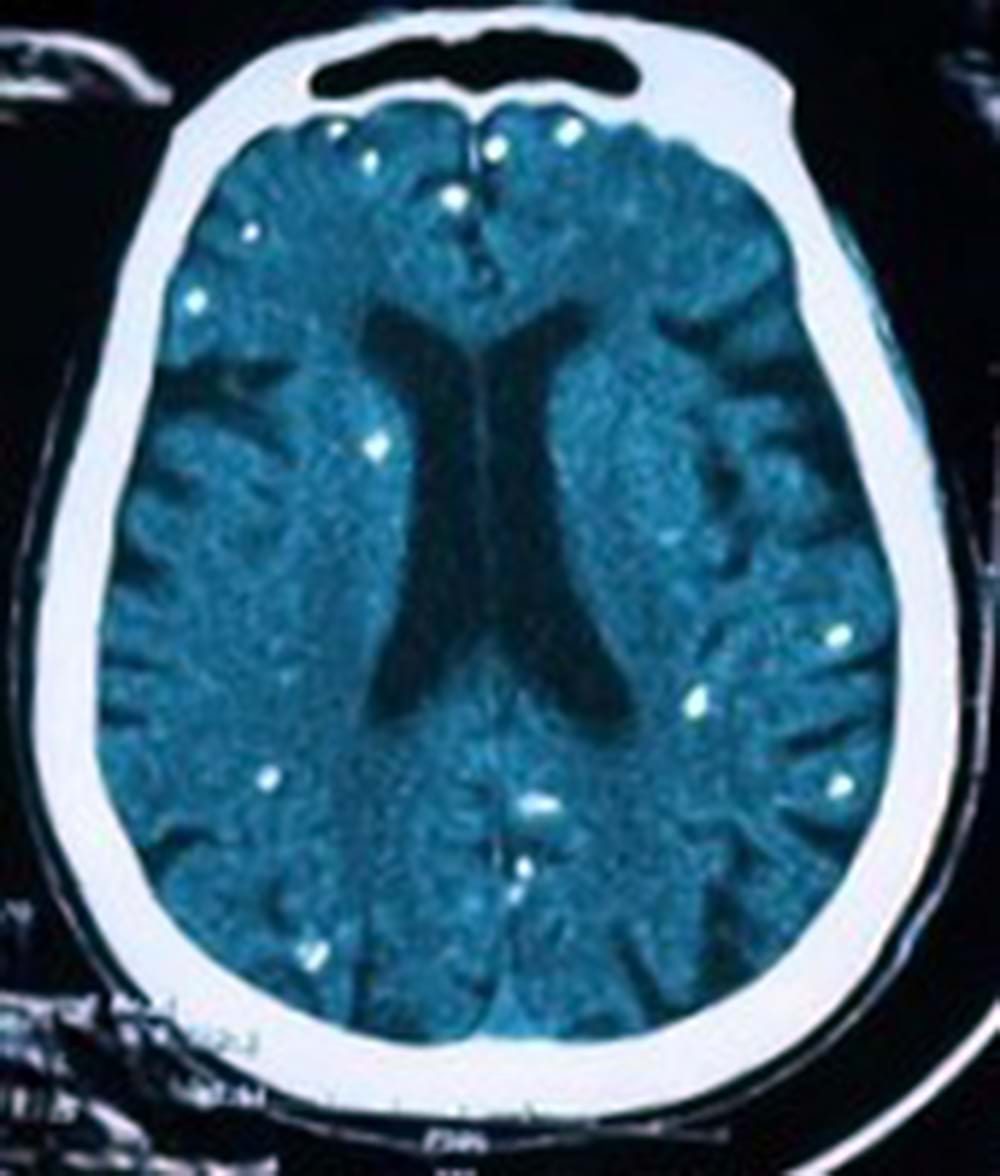

Gần đây khoa Hồi sức truyền nhiễm - Viện Lâm sàng các bệnh Truyền nhiễm (Bệnh viện Trung ương Quân đội 108) tiếp nhận một người bệnh nữ sinh năm 1948 được chẩn đoán theo dõi nhiễm ấu trùng sán dây lợn. Người bệnh được chuyển lên từ tuyến trước vì rối loạn ý thức đe dọa suy hô hấp, hình ảnh cắt lớp vi tính sọ não và X-quang ngực cho thấy rất nhiều nốt cản quang trong nhu mô não và dưới da vùng ngực-bụng.

Nhiều nốt cản quang trong nhu mô não của người bệnh

Người bị nhiễm sán lợn do ăn phải nang sán trong thịt lợn gạo không nấu chín hoặc trứng sán có trong rau sống. Ở người, ngoài vị trí cơ, nang sán có thể được hình thành tại các vị trí nguy hiểm như não, mắt, và có thể gây ra các triệu chứng tại cơ quan này như động kinh, rối loạn tâm thần - vận động, đau đầu, đau mắt, giảm thị lực, … Nang sán dây lợn có thể tự thoái hóa hoặc bị vôi hóa, tạo nên nhiều hình ảnh cản quang phát hiện được trên phim X-quang như trường hợp bệnh nhân trên.